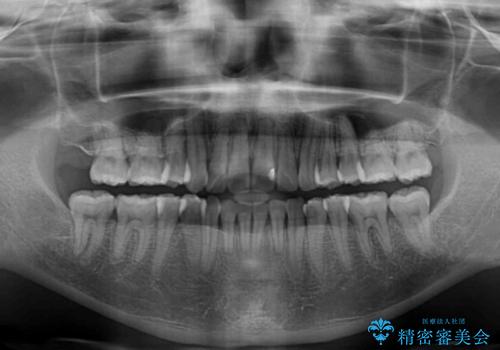

内側にある歯が邪魔 重なった前歯の歯列矯正

- 重なった前歯を邪魔に感じ、汚れも溜まりやすいことを気にして来院された患者様です。

右上前から2番目の歯が内側に転位しているため、上顎の正中は右にずれていました。

右上4番目の歯を抜歯し、上顎裏側に補助装置を装着して左の歯列全体を後方に移動させながら、正中を合わせるようにして行くこととしました。

内側に転位していた歯はきれいに歯列に収まり、清掃性が著しく改善しました。

元々神経の失活してしまっている前歯2本は変色が目立つようになってきたため、今後セラミッククラウンによる補綴治療を行う予定です。